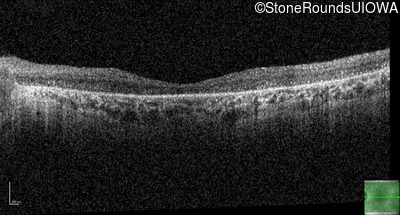

Optical Coherence Tomography - Right - 10/140 sc

Exemplar / OCT Stack